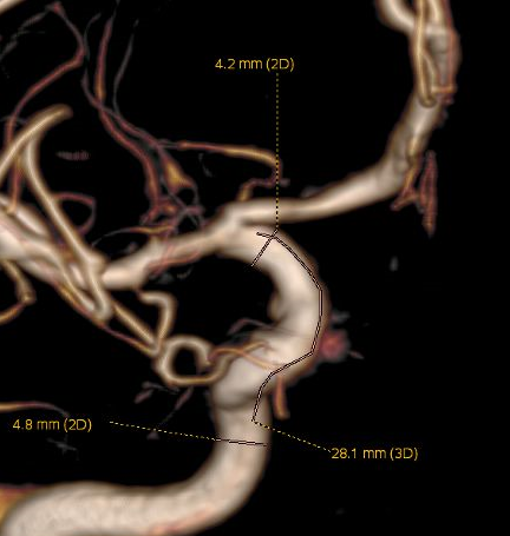

左侧瘤体形态欠规则,4mm×30mm Streamline 优先处理左侧动脉瘤

脑血管造影提示右侧颈内动脉颅内段多发动脉瘤(反主动脉弓)

脑血管造影提示右侧颈内动脉颅内段多发动脉瘤

4mm×30mm Streamline

术后4月余随访:多发动脉瘤均未见显影,远端残余轻度狭窄